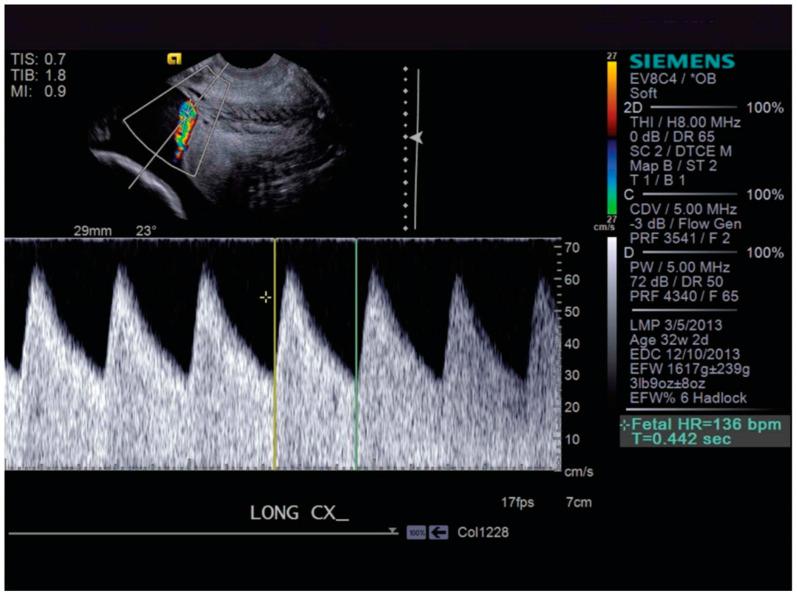

Vasa previa is a pregnancy complication that occurs when unprotected fetal blood vessels traverse the cervical os, placing the fetus at high risk of exsanguination and fetal death. These fetal vessels may be compromised by fetal movement and compression, leading to poor oxygen distribution and asphyxiation. Diagnostic tools for vasa previa management and preterm labor (PTL) include transvaginal ultrasound, cervical length (CL) surveillance and use of fetal fibronectin (FFN) testing. These tools can prove to be quite useful as they allow for lead time in the prediction of PTL and spontaneous rupture of membranes which can result in devastating outcomes for pregnancies affected by vasa previa. We conducted a literature review on vasa previa management and the usefulness of FFN and CL surveillance in predicting PTL and found 36 related papers. Although there is limited research available to show the impact of FFN and CL surveillance in the management of vasa previa, there is sufficient evidence to support FFN and CL surveillance in predicting the onset of PTL, which can have devastating consequences for the pregnancies affected. It can be extrapolated that these tools, by helping to determine pregnancies at risk for PTL, could improve management and outcomes in patients with vasa previa. Future studies investigating the management of vasa previa with FFN and CL surveillance to reduce the burden of PTL and its associated comorbidities are warranted.

前置血管是一种妊娠并发症,当未受保护的胎儿血管穿过宫颈内口时就会发生,使胎儿面临大量失血和死亡的高风险。这些胎儿血管可能会因胎儿活动和受压而受损,导致氧气分布不良和窒息。前置血管管理和早产(PTL)的诊断工具包括经阴道超声、宫颈长度(CL)监测以及使用胎儿纤连蛋白(FFN)检测。这些工具可能非常有用,因为它们能在预测PTL和胎膜早破方面争取到提前时间,而胎膜早破可能会给受前置血管影响的妊娠带来灾难性后果。我们对前置血管管理以及FFN和CL监测在预测PTL方面的有用性进行了文献综述,共找到36篇相关论文。尽管关于FFN和CL监测在前置血管管理中的影响的研究有限,但有足够的证据支持FFN和CL监测在预测PTL发作方面的作用,PTL发作可能会给受影响的妊娠带来灾难性后果。可以推断,这些工具通过帮助确定有PTL风险的妊娠,可能会改善前置血管患者的管理和结局。有必要开展未来研究,探讨使用FFN和CL监测来管理前置血管,以减轻PTL及其相关合并症的负担。